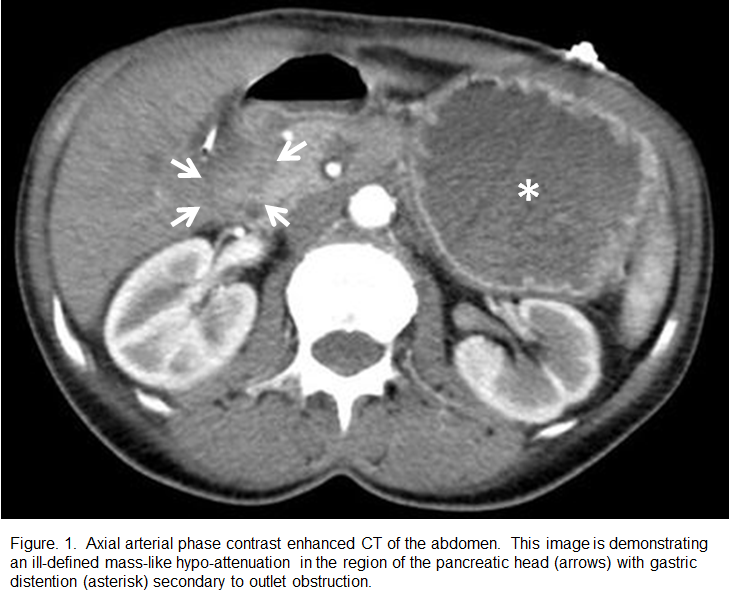

Ductal adenocarcinoma of the pancreas is the most common malignant tumor of the exocrine pancreas and accounts for greater than 90% of pancreatic malignancies.1 Pancreatic cancer is an insidious entity, which is commonly asymptomatic until late in the disease course. The most common clinical signs and symptoms are progressive jaundice, weight loss, abdominal pain, and back pain.2 Common laboratory findings include disturbances in liver function tests indicative of biliary obstruction as well as elevated tumor markers, such as CA 19-9, CEA, and CA 242. Imaging is an important component of the diagnosis, with Computed Tomography (CT) commonly showing a poorly marginated hypoattenuating and non-enhancing pancreatic head mass with adjacent structural invasion. Surgical resection with pancreaticoduodenectomy or regional pancreatectomy is the only potentially curable treatment, however only 15 to 20 percent of patients are candidates due to late presentation with local vascular invasion and/or metastatic disease. We report a case of a 48-year-old female with an atypical clinical presentation that was treated for other causes without success, and ultimately presented with duodenal obstruction secondary to a pancreatic head ductal adenocarcinoma. The patient was a surgical candidate and had a pancreaticoduodenectomy for treatment of the disease. Prognosis is poor - overall survival is less than 10 percent, and less than five percent survive five years without surgery.References